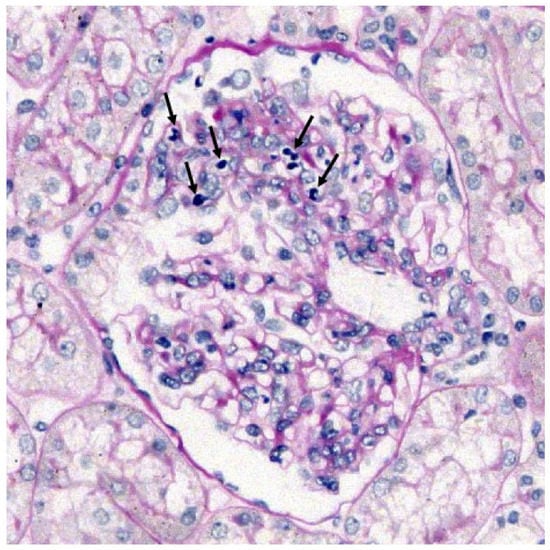

| Glomeruli with leukocytes (%) | 8 (57) | 6 (10) | 8 (21) | 0.0008 b |

| M1 (%) | 71 | 68 | 95 | 0.0075 b 2 vs. 3 = 0.006 |